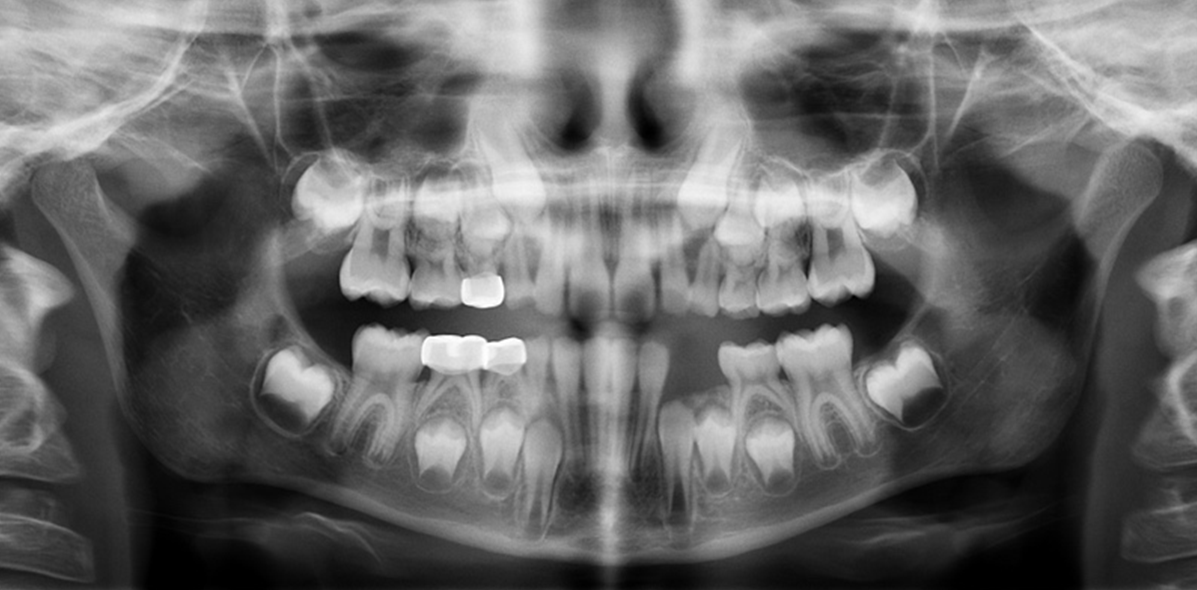

1. How old is the patient with the following X ray?